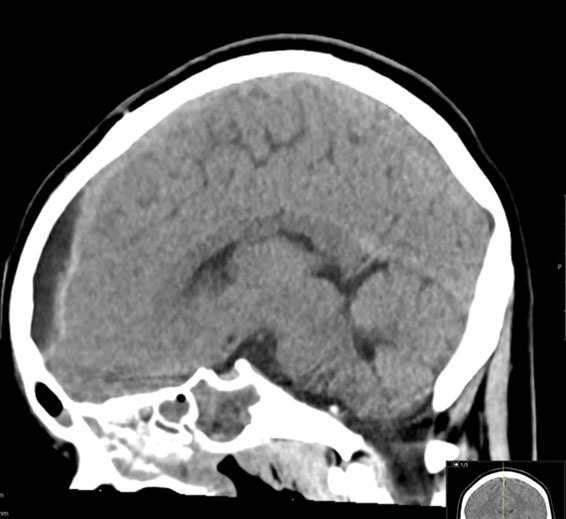

Symptoms typically have an indolent onset, starting with low fevers and headache, and progressing to vomiting and neurologic changes. A head CT or magnetic resonance imaging (MRI) of the brain allows for an accurate diagnosis. See Figures 9 A-B for a brain MRI that depicts the typical findings of abscesses secondary to Streptococcus. Figures 10 A-C show a classic epidural abscess. Given the possibility of elevated intracranial pressure, lumbar puncture should be avoided because of the risk of herniation.

Figure 10A. Epidural Abscess |

![]() |

Axial contrast-enhanced computed tomography of a midline epidural abscess Used with permission from Mark Warren, DO, Dayton Children’s Hospital. |

Figure 10B. Epidural Abscess |

Sagittal contrast-enhanced computed tomography of a midline epidural abscess Used with permission from Mark Warren, DO, Dayton Children’s Hospital. |